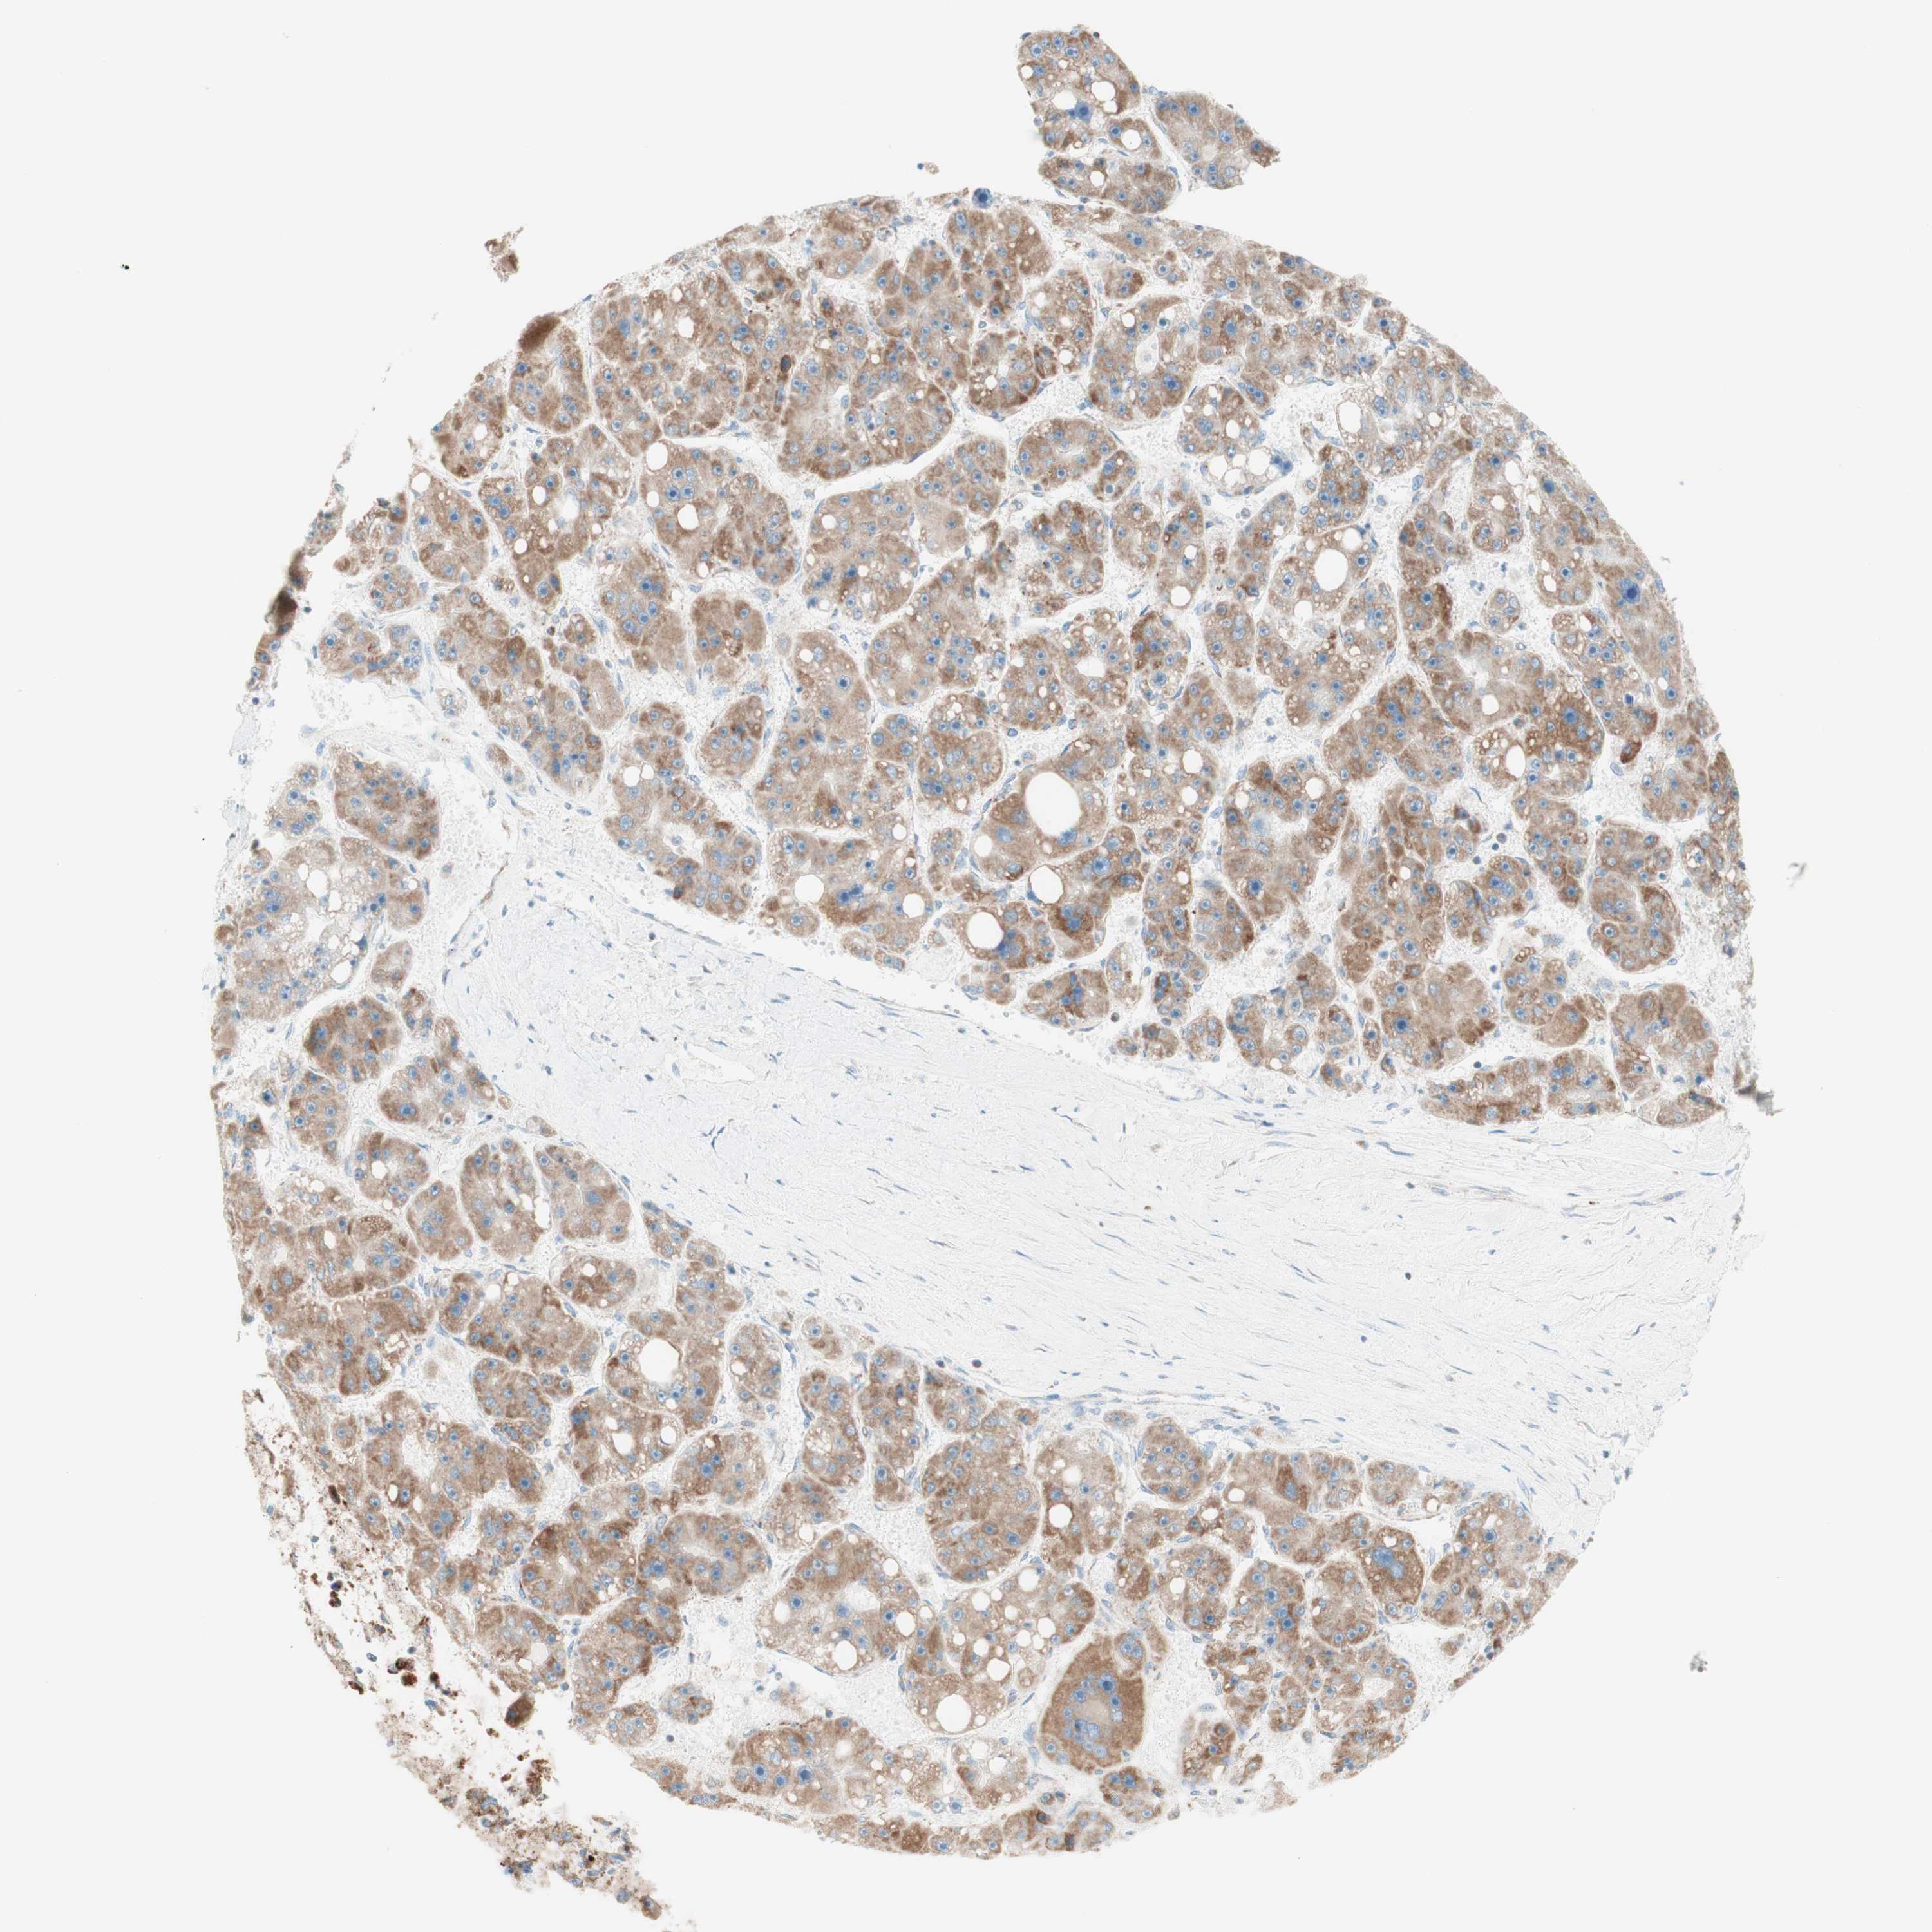

LIVER CANCER - Protein expressioni

A mouse-over function shows sample information and annotation data. Click on an image to view it in a full screen mode. Samples can be filtered based on level of antibody staining by selecting one or several of the following categories: high, medium, low and not detected. The assay and annotation is described here.

Note that samples used for immunohistochemistry by the Human Protein Atlas do not correspond to samples in the TCGA dataset.

Antibody stainingi

Antibody staining in the annotated cell types in the current human tissue is reported as not detected, low, medium, or high, based on conventional immunohistochemistry profiling in selected tissues. This score is based on the combination of the staining intensity and fraction of stained cells.

Each image is clickable and will lead to virtual microscopy that enables deeper exploration of all samples and also displays staining intensity scores, fraction scores and subcellular localization as well as patient and tissue information for each sample.

Antibody HPA011562

Antibody CAB005585

Staining

High

Medium

Low

Not detected

Intensity

Strong

Moderate

Weak

Negative

Quantity

>75%

75%-25%

<25%

None

Location

Nuclear

Cytoplasmic/membranous

Cytoplasmic/membranous,nuclear

Cholangiocarcinoma

Carcinoma, Hepatocellular, NOS